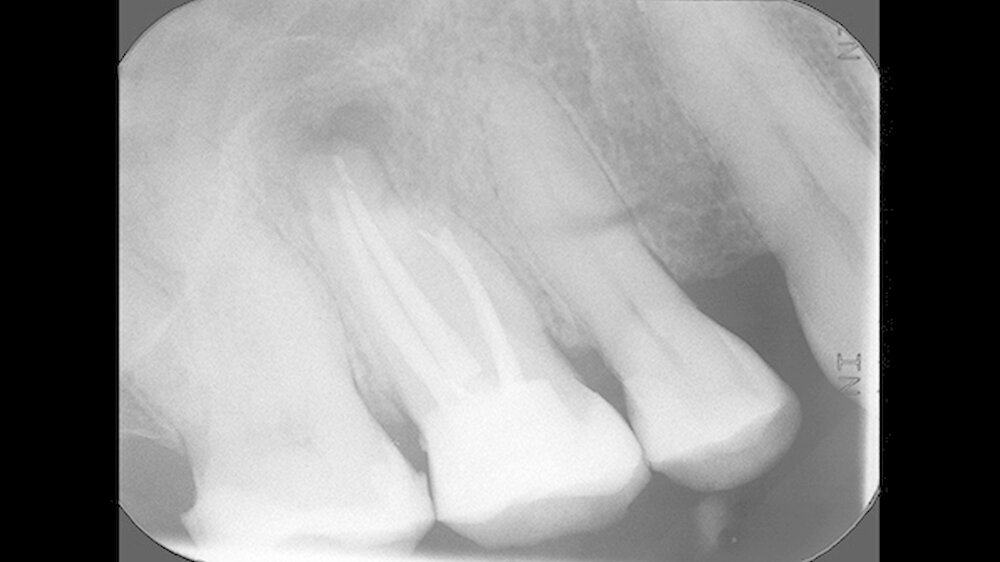

Er berichtete, dass an diesem Zahn ungefähr ein Jahr zuvor eine Wurzelkanalbehandlung alio loco durchgeführt worden war. Das angefertigte Röntgenbild (Abbildung 1) zeigte eine apikale Aufhellung und ein frakturiertes Wurzelkanalinstrument, das vermutlich über den Apex des mesiobukkalen Wurzelkanals herausragte. Die Füllung aller vier Wurzelkanäle erschien röntgendicht, wandständig und ohne Zeichen von Porositäten oder Lufteinschlüssen.